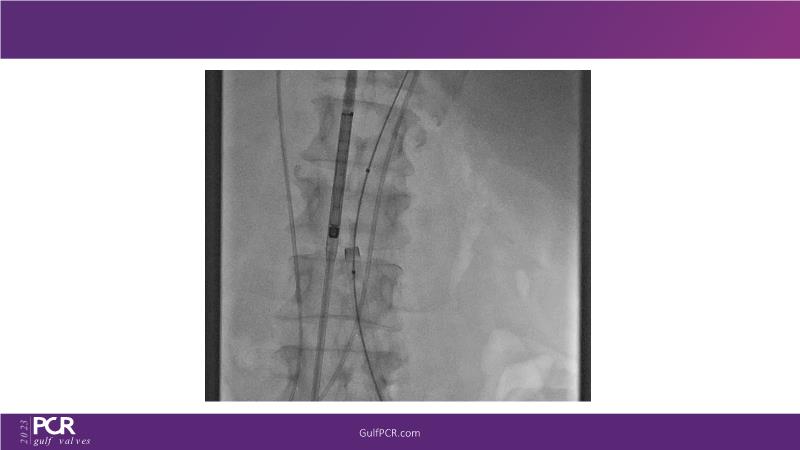

The primary focus of this GulfPCR-GIM 2023 session revolves around pre-procedural planning considerations, valve selection, and managing complex anatomies using both traditional self-expanding valves and the Evolut FX system. Additionally, the session aims to explore the work-up protocol for patients grappling with severe AS and advanced CKD, elucidate the algorithm for selecting the appropriate TAVR platform, discuss strategies to reduce contrast utilization, and highlight the distinctive advantages offered by the Evolut FX system.

• To learn more about optimization of valve deployment